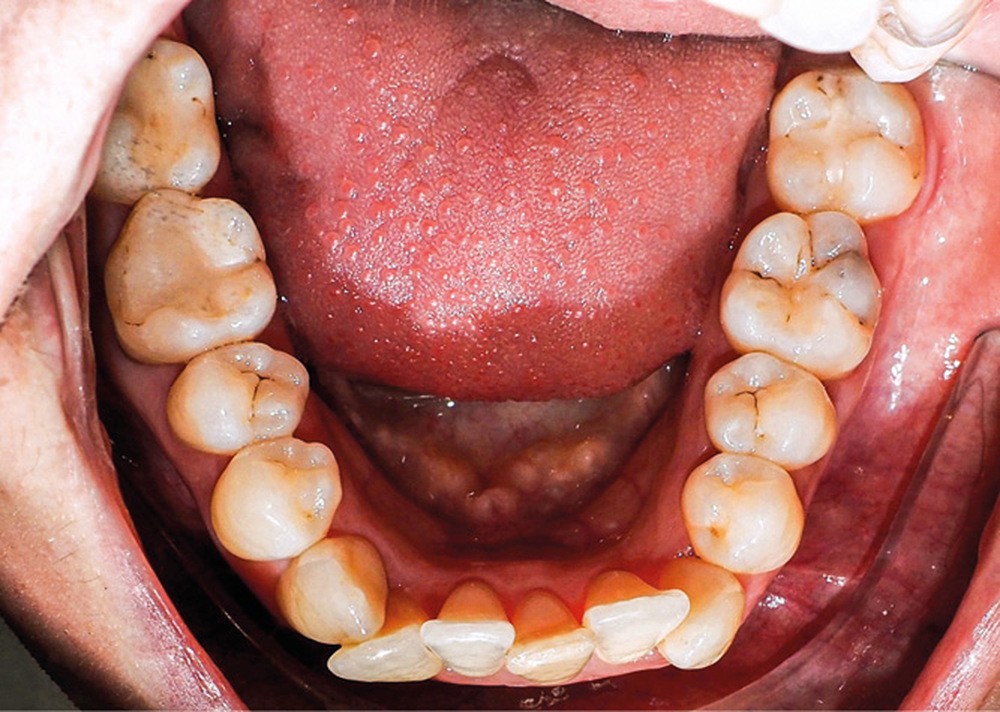

Examen endo-buccal (fig. 2a-e)

L’arcade maxillaire est parabolique, la 12 présente une légère mésio-rotation. L’arcade mandibulaire est également parabolique avec un encombrement antérieur estimé à 6 mm. On note une dyschromie de la 31, dont le test de vitalité est négatif. Le parodonte est fin.

En occlusion, on note une relation de Classe I molaire bilatérale avec un surplomb normal et une supraclusion. Les médianes incisives sont concordantes.

Les incisives maxillaires sont de forme triangulaire [1] et l’indice de Bolton est de 97 % qui traduit la présence d’une DDD par excès mandibulaire.